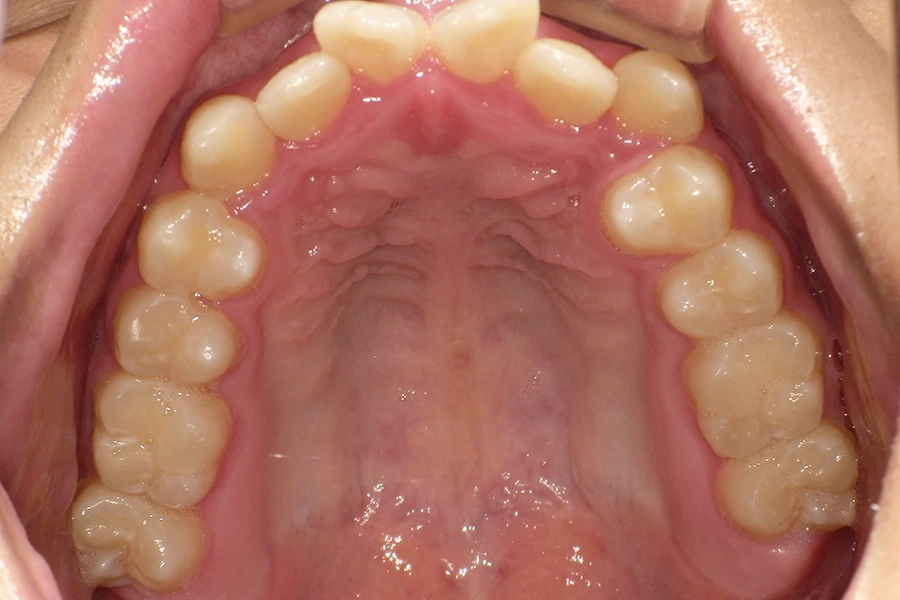

上顎

Before

After

治療前は上から見ると、前歯部分のアーチが乱れているのが分かりますね。

治療後は上から見ると、前歯部分のアーチがきれいに整っているのが一目で分かります。